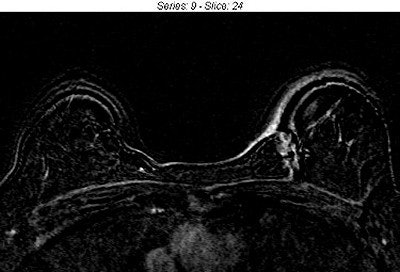

Artifacts due to patient movement

In addition to the amount of data that must be analyzed, breast MRI is challenging because patient movement can lead to registration errors that produce pseudo-enhancement, mimicking ductal carcinoma in situ (DCIS) and even a suspicious enhancing mass in subtraction images. In some cases, these pseudo-lesions are sent for biopsy, increasing patient anxiety and costs.

| Breast MRI image before (above) and after (below) registration. Patient had a left lumpectomy for infiltrating ductal carcinoma. Motion artifacts in the image before registration increase the risk that normal structures could be misinterpreted as DCIS and obscure the skin margins. |

| The image after registration more clearly shows the expected normal enhancement around the surgical margin. Misregistration at the skin margin is also greatly reduced.Image courtesy of First Hill Diagnostic Imaging, Seattle, and Confirma, Kirkland, WA. |